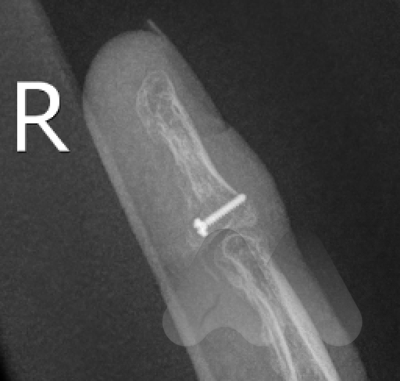

Treatment

Treatment is time critical and you should see your doctor to organise an ultrasound of the finger and a referral to a hand surgeon within 1 week of injury. This condition requires surgery to reattach the flexor tendon. If there is a delay in diagnosis, the tendon may not be able to be repaired and other more complex reconstructive surgeries may be required.